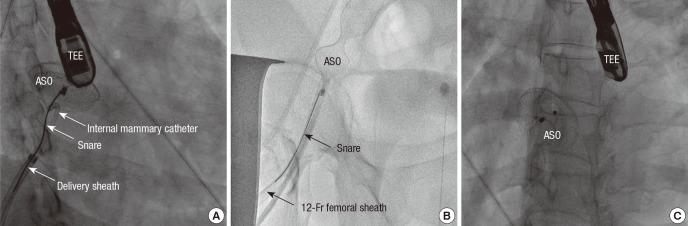

Percutaneous device closure for secundum atrial septal defects (ASDs) has been performed commonly and safely with high success rates. However, it is still challenging to close ASDs that are surrounded with deficient or hypermobile rims and could be compromised with an unexpected migration of device. We report a case of percutaneous Amplazter Septal Occluder (ASO; St. Jude Medical Inc., St. Paul, Minnesota, USA) device closure for an ASD with a thin and floppy interatrial septum, which immediately migrated into the right atrium and was not pulled back into the delivery sheath. To our knowledge, this is the first report on a successful percutaneous retrieval and redeployment of the device in such a situation, preventing any vascular injury or unplanned emergency open heart surgery.